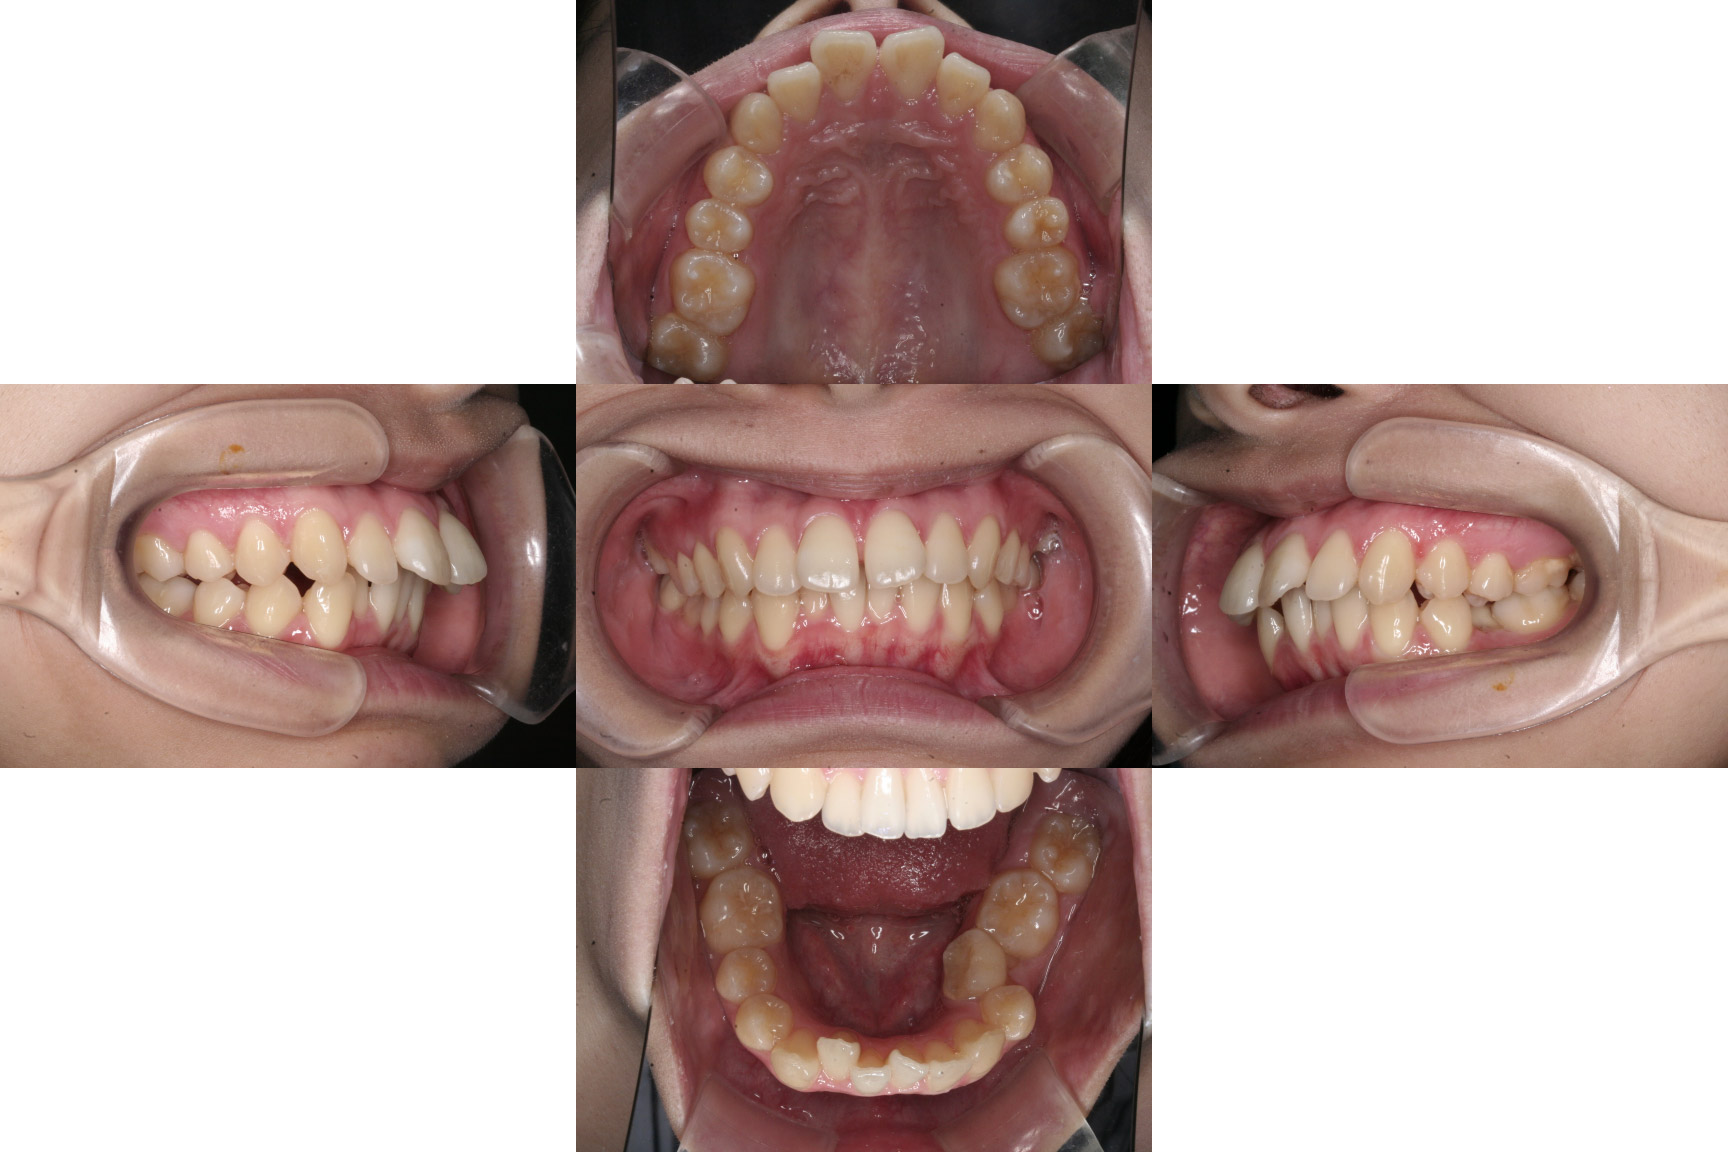

Before

初診